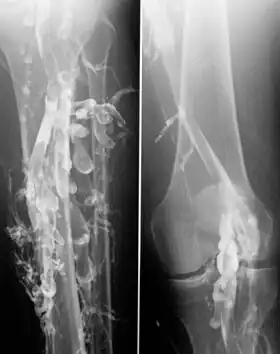

![]() Venography in a patient with deep vein thrombosis | |

Contrast venography is the gold standard for judging diagnostic imaging methods for deep vein thrombosis; although, because of its cost, invasiveness, and other limitations this test is rarely performed.[1]